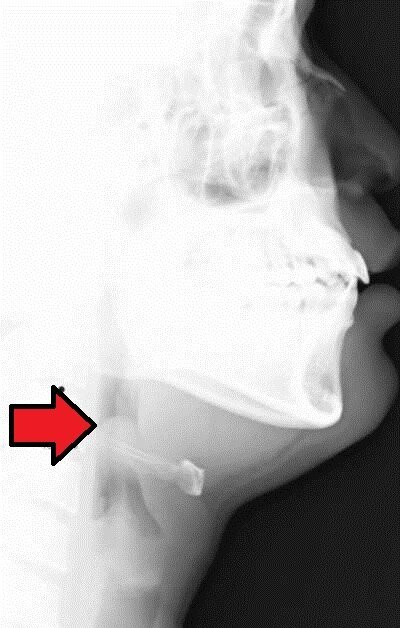

Thumb Sign bei Epiglottitis

Abb. 4: Laterales Halsröntgen — Thumb Sign: verdickte Epiglottis. Quelle: Wikimedia Commons